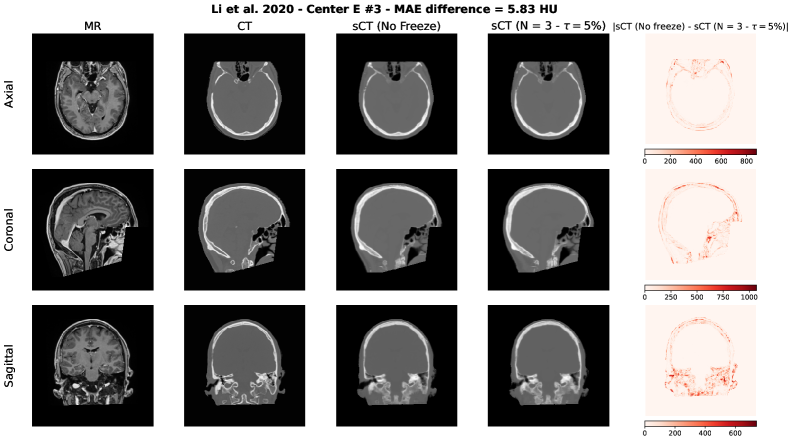

To qualitatively assess the potential impact of the adaptive freezing strategy on the generated synthetic CTs (sCTs), we conducted a visual comparison between the sCTs obtained with and without the proposed methodology. For each model employed in the study, we selected two representative test cases based on the following criteria:

• The case with the minimum difference in terms of MAE, thus the lowest difference between the sCTs MAE generated with and without adaptive freezing.

• The case with the maximum difference in terms of MAE, thus the highest difference between the sCTs MAE generated with and without adaptive freezing.

Each figure presents the following for the axial, coronal and sagittal plane of the central slice:

1. 1.

Input MR image;

2. 2.

Ground-truth CT image;

3. 3.

sCT generated without adaptive freezing;

4. 4.

sCT generated with the proposed adaptive freezing, using 𝒩=3\mathcal{N}=3 and τ=5%\tau=5\%;

5. 5.

Absolute difference map between the two sCTs.

Figure S4: Li et al. architecture [36] – Maximum MAE difference case.

Refer to caption

Across all models and both selected cases, no relevant and systematic structural differences were observed. The differences highlighted in the absolute difference maps and the variation in MAE are attributable to the stochastic nature of the training process (e.g., batch shuffling and optimization path variability) rather than the direct effect of the adaptive freezing mechanism.

This findings are aligned with the results observed in terms of MAE, PSNR and SSIM presented in this study.